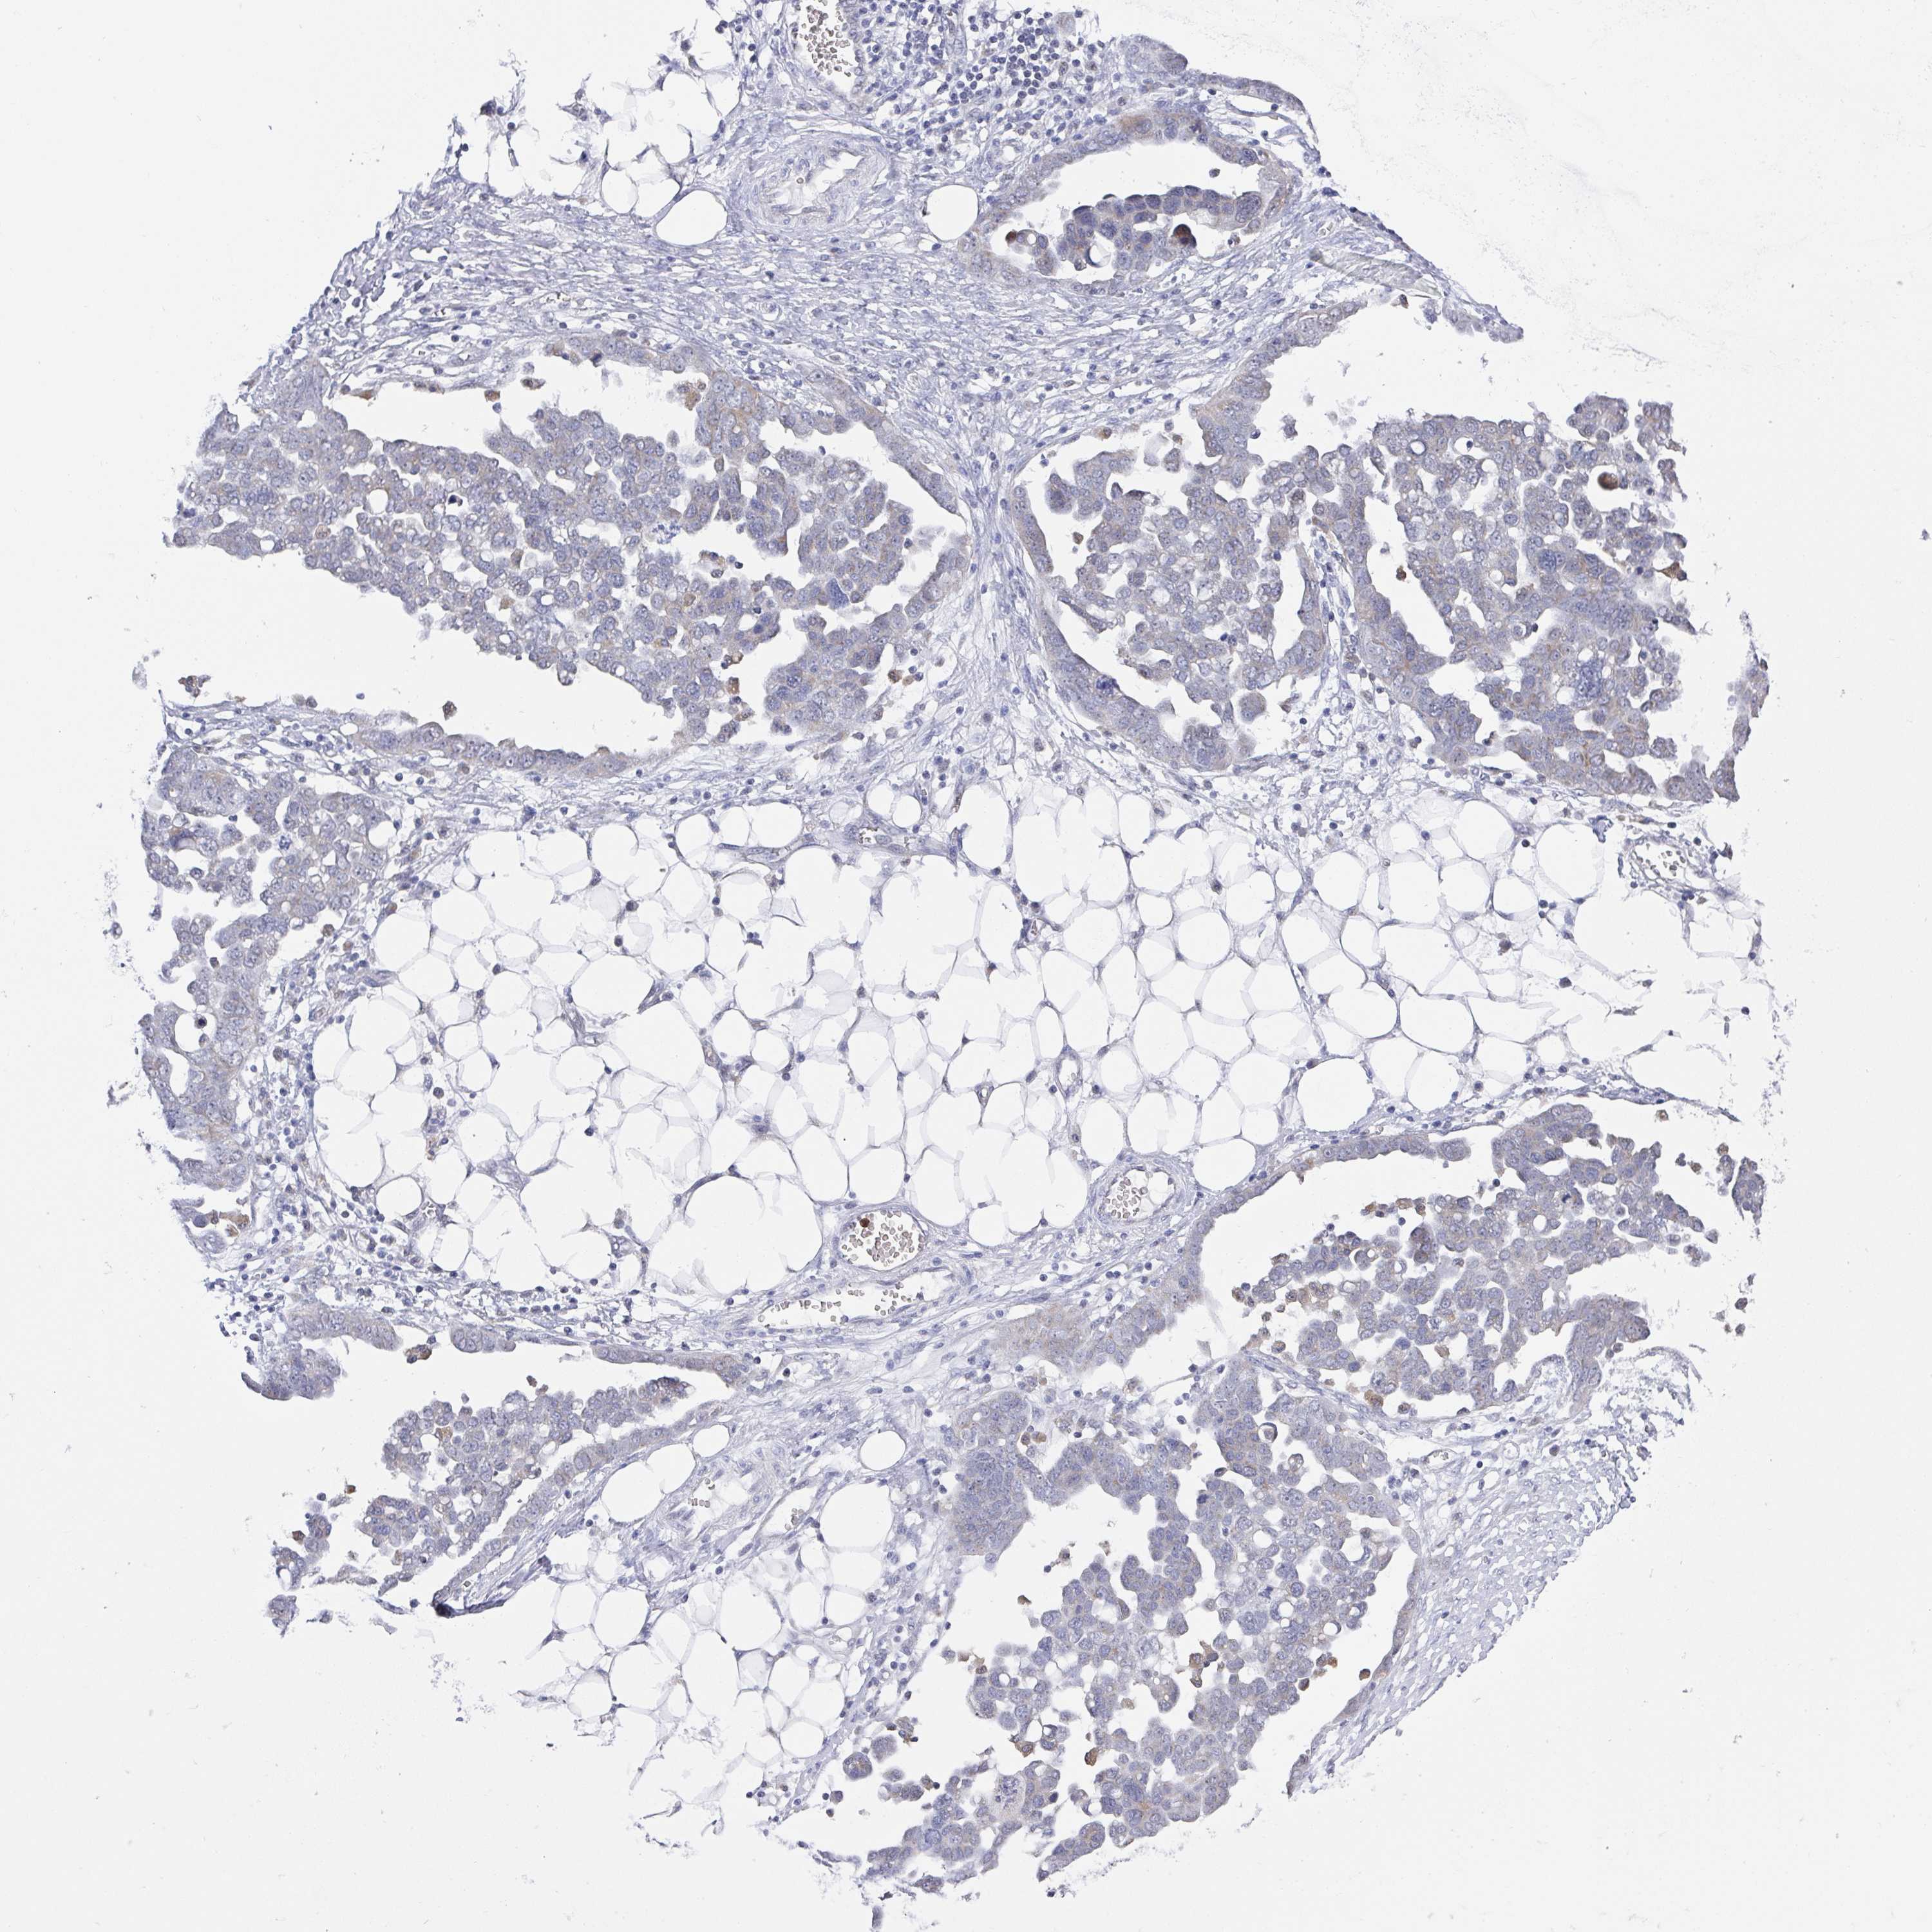

OVARIAN CANCER - Protein expressioni

A mouse-over function shows sample information and annotation data. Click on an image to view it in a full screen mode. Samples can be filtered based on level of antibody staining by selecting one or several of the following categories: high, medium, low and not detected. The assay and annotation is described here.

Note that samples used for immunohistochemistry by the Human Protein Atlas do not correspond to samples in the TCGA dataset.

Antibody stainingi

Antibody staining in the annotated cell types in the current human tissue is reported as not detected, low, medium, or high, based on conventional immunohistochemistry profiling in selected tissues. This score is based on the combination of the staining intensity and fraction of stained cells.

Each image is clickable and will lead to virtual microscopy that enables deeper exploration of all samples and also displays staining intensity scores, fraction scores and subcellular localization as well as patient and tissue information for each sample.

Antibody HPA047836

Antibody HPA052095

Antibody CAB004524

Staining

High

Medium

Low

Not detected

Cystadenocarcinoma, serous, NOS

Carcinoma, endometroid